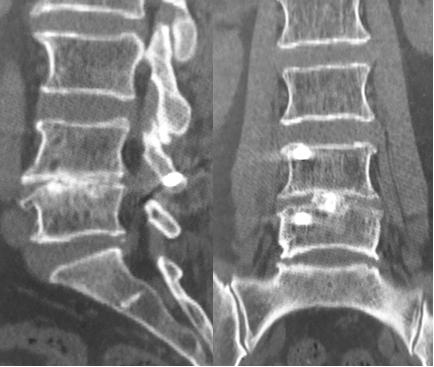

椎间盘突出椎体塌陷

经皮微创完成手术,切口仅3cm长,一个洞完成3枚螺钉植入及减压、融合。